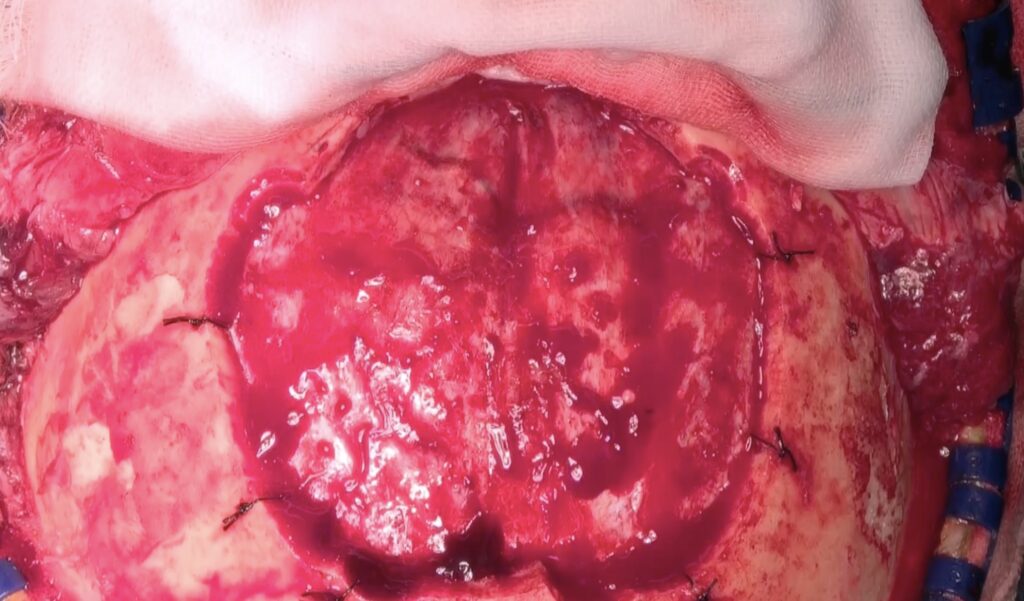

両側前頭開頭でSSS前端を結紮切断。Orbitaは外さず。